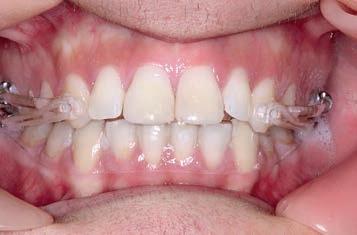

By the end of the first month of sagittal correction, there was already evidence of some derotation of the upper first molar and movement of the buccal segment (molars, premolars and canines) toward a Class I occlusion. Space was also beginning to open between the upper incisors. After

3 months of sagittal correction, the occlusal lock of the Class I platform had been accomplished (Sagittal First) and the case was ready to progress to the next stage. The Motion appliance was removed. While in this case, it would have been easy to finish the case with Invisalign, the patient chose fixed appliances so Carriere SLX .022 PSL brackets were bonded.